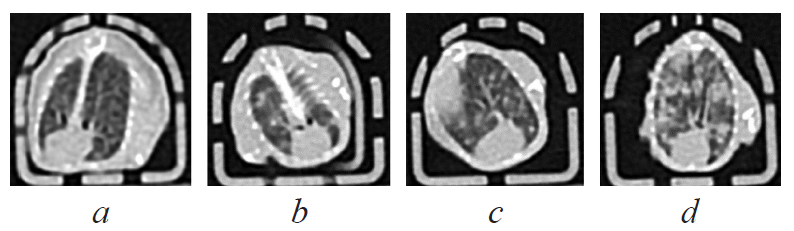

RESULTS: Tumor was developed at the site of primary transplantation in all mice from groups 3 and 4, which was confirmed by visual assessment and the results of histological examination. Tumor growth in the main group was significantly less than in the control group of the tumor, which may be due to intoxication against the background of tuberculosis infection. All infected mice from groups 2 and 4 developed pulmonary tuberculosis, confirmed by computed tomography of the lungs, bacteriological and histological examination of lung samples. Mycobacterial load in the lungs was the highest in animals with concomitant pathology of tuberculosis and tumor. The survival rate of mice was determined to a large extent by tumor growth rather than by the progression of tuberculosis infection.